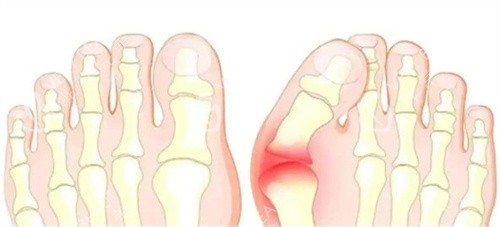

苏敬达的诊疗范围十分广泛,除了核心的拇外翻矫正与失败修复,还涵盖宽足缩窄、长趾缩短、足趾畸形矫正、足型美化等多个足部项目。

比如有些人不仅有拇外翻,还伴随足型过宽影响穿鞋美观,苏敬达能在矫正拇外翻的同时,结合宽足缩窄项目进行改善;对于足趾长短不一、形态畸形的情况,也能通过正规诊疗进行调整,让足部形态更协调。

以拇外翻轻重程度划分,轻度大脚骨矫正 12800 元起,中度大脚骨矫正 28000 元起,重度大脚骨矫正 50000 元起。

对于重视性价比的患者,轻度拇外翻 12800 元起的价格友好,不会造成过大经济压力;对于足部问题较复杂的重度拇外翻患者,他的正规修复能力能提供有力支撑。